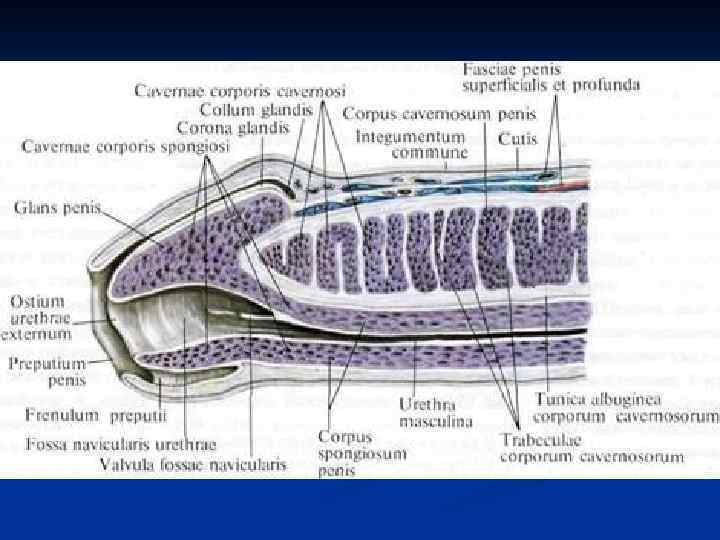

Половой член, penis: 1. Головка, glans penis 2. Тело, corpus penis 3. Корень, radix penis

Половой член, penis: 1. Головка, glans penis 2. Тело, corpus penis 3. Корень, radix penis

Половой член покрыт кожей (1), cutis которая на нижней поверхности образует шов, raphe penis. В переднем отделе выраженная кожная складка – крайняя плоть (2), preputium penis формирующая препуциальный мешок, saccus preputium. Внутренняя поверхность крайней плоти соединена с головкой (3), glans penis уздечкой крайней плоти, frenulum preputii в области ладьевидной ямки мочеиспускательного канала (4), fossa navicularis uretrae. В полость препуциального мешка железы крайней плоти, glandulae preputialis выделяют смегму (препуциальный жир).

Половой член покрыт кожей (1), cutis которая на нижней поверхности образует шов, raphe penis. В переднем отделе выраженная кожная складка – крайняя плоть (2), preputium penis формирующая препуциальный мешок, saccus preputium. Внутренняя поверхность крайней плоти соединена с головкой (3), glans penis уздечкой крайней плоти, frenulum preputii в области ладьевидной ямки мочеиспускательного канала (4), fossa navicularis uretrae. В полость препуциального мешка железы крайней плоти, glandulae preputialis выделяют смегму (препуциальный жир).